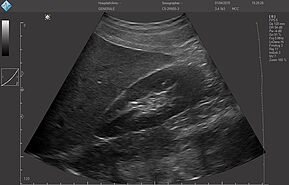

Исследование FAST (Сфокусированная сонографическая оценка при травме) позволяет выявить наличие жидкости в предполагаемых клинических условиях, визуализируя 10 структур или пространств в четырех областях:

- Перикардиальной

- Околопеченочной

- Околоселезеночной

- Тазовой

E-FAST (расширенный-FAST) дополнительно обследует переднюю и боковую плевральную полость (торакальная проекция) для оценки наличия пневмоторакса или плеврального выпота, предположительно гемоторакса у пациентов с травмой.

E-FAST имеет высокую чувствительность и специфичность (особенно в условиях гипотонии), может быть выполнен быстро, неинвазивно, без лучевой нагрузки, и может проводиться повторно. Благодаря таким преимуществам ультразвук по существу заменил диагностический перитонеальный лаваж (ДПЛ) при обследовании пациентов с травмой.

Положительный E-FAST у гемодинамически нестабильного пациента может указывать на необходимость проведения немедленного вмешательства (например, зондовой торакостомии, перикардиального окна, диагностической лапаротомии).

У гемодинамически стабильного пациента расширенная фокусированная оценка с сонографией при травме (E-FAST) может направлять дальнейшие диагностические исследования.

Хотя неотложный ультразвуковой протокол E-FAST был разработан для ускорения оказания помощи пострадавшим пациентам, применение его компонентов оказалось эффективным в случае использования портативного аппарата УЗИ (point-of-care ultrasound - POCUS) для обследования неповрежденных пациентов с гипотензией с целью выявления свободной жидкости, образовавшейся по другим причинам (например, при разрыве при внематочной беременности, аневризме брюшной аорты).